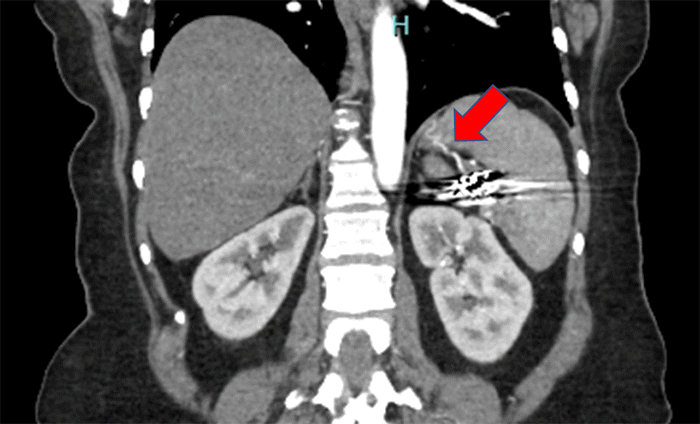

To aid in decision-making, a recent computed tomography angiography (CTA) was performed and the radiologist confirmed the presence of adequate collateral vessels (Figure 1). The patient was thoroughly counseled regarding the potential outcomes of the surgery, including the possibility of:

Figure 1. Collateral Splenic Blood Flow Post-SAE. Published with Permission

CTA revealing collateral blood flow to the spleen, with artifact due to prior embolization material